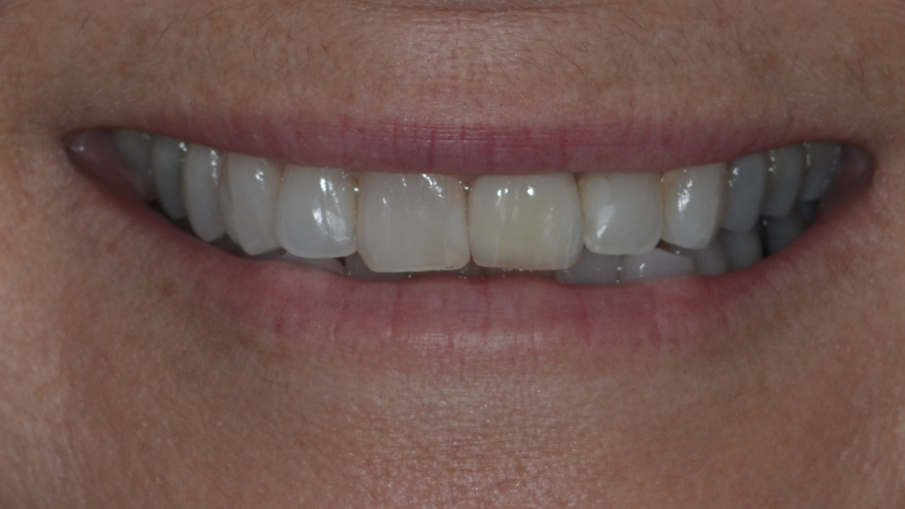

La protesi finale è stata progettata utilizzando Straumann CARES Visual con un workflow digitale. Durante la fase di progettazione è stato possibile vedere che il foro di accesso della vite sarebbe rimasto completamente sul lato palatale senza alcuna interferenza con l’estetica del restauro. Una corona monolitica in ceramica (Prettau Zirconia, Zirkonzahn) è stata fresata e cementata fuori dalla bocca su un’ampia base regolare Variobase (Straumann) con un’altezza gengivale di 1,5 mm, corrispondente al rimodellamento terapeutico dell’architettura ossea (Fig. 30). Dopo il controllo dell’occlusione, dei punti di contatto e dei movimenti di escursione, il restauro è stato inserito e avvitato con un torque di serraggio 25 Ncm (Figg. 31–33).

Fig. 31_Risultato finale del sorriso.

La paziente era infermiera odontoiatrica in uno studio dentistico e quindi interagiva direttamente con molti pazienti durante i suoi turni di lavoro. Per lei è stato molto gratificante poter lasciare la poltrona sapendo che il dente compromesso era stato estratto e che l’impianto era stato posizionato e immediatamente protesizzato. La corona finale corrispondeva alla struttura e alla tonalità dei denti adiacenti, dando armonia al sorriso. Il paziente valutava la corona finale come “la ciliegina sulla torta”.